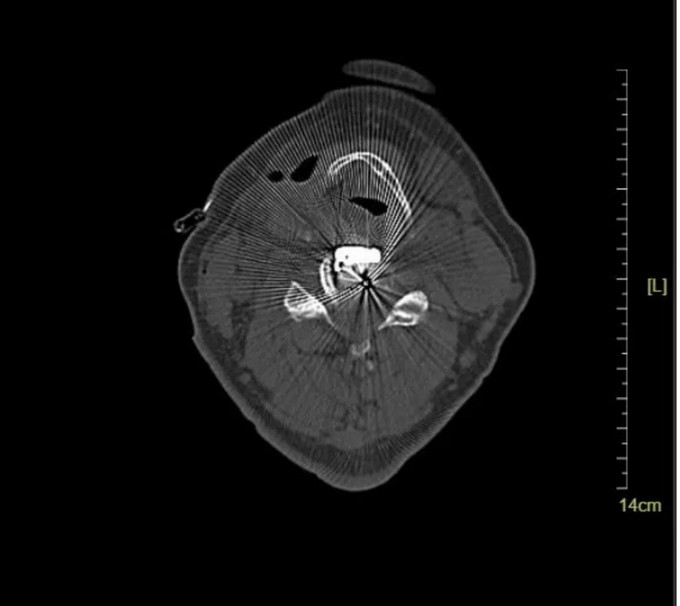

頸椎CT橫斷位 可以看到明顯突出的骨贅

頸椎CT橫斷位 可以看到突出的骨贅已被切除